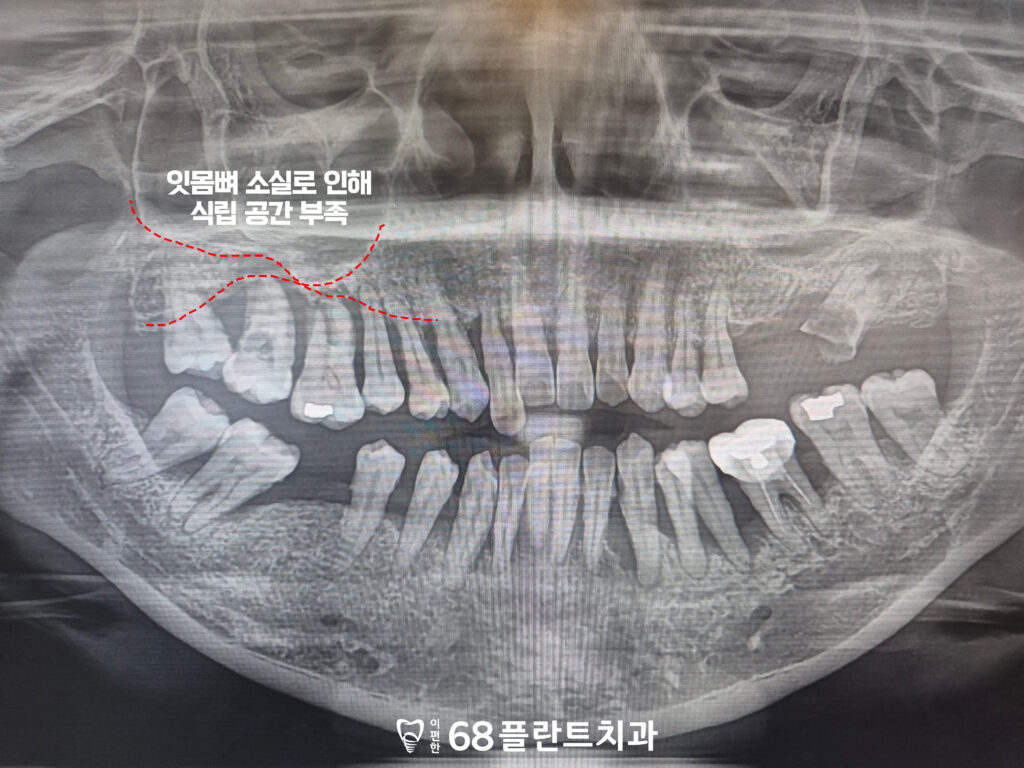

23.04.05

그래서 전체적인 임플란트 치료가

필요했습니다.

하지만 광범위한 잇몸뼈의 소실로 인해

임플란트를 식립할 공간이

부족했습니다.

이 경우, 단순히 임플란트를

식립하는 것만으로는

안정적인 고정이 어려울 수 있기 때문에,

뼈 이식을 통해 소실된 뼈를 보충하고

임플란트를 고정할 충분한 공간을

확보하는 것이 필요했습니다.